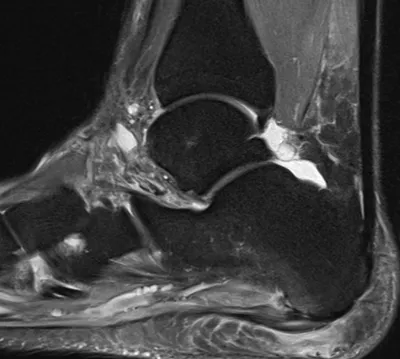

This collection contains 3 radiology images related to plantar fascia, including various imaging modalities such as X-rays, MRIs, CT scans, and ultrasound images commonly used in medical diagnosis and education.